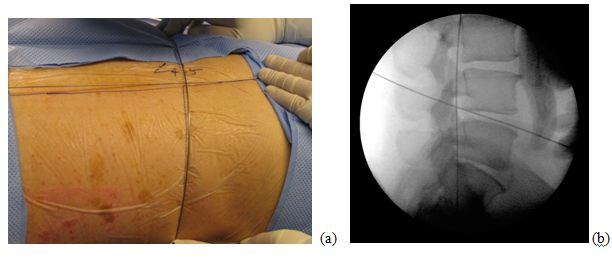

A 63-year-old patient with morbid obesity and insulin dependent diabetes mellitus suffered from spinal canal stenosis and multiple level disc protrusions at L2/3, L3/4, L4/5 and L5/S1. The largest disc was at L5/S1, > 6mm as illustrated below. His weight is 280 lbs and height 5’ 8” (Figure 4–16). The patient complained of back pain and radicular symptoms including the anterior and surface of both thighs and legs, and back of the foot with more severe pain on the right side associated with some neurogenic claudication. Previously the patient refused open surgery with fusion, because of increased risk in morbid obese and diabetic patients and requiring a multi level extensive open spinal fusion. After reviewing his MRI scans, (Figure 4) minimally invasive endoscopic microdecompression surgery was recommended to the patient as a solution for his spinal condition. He agreed to proceed with MISS surgery. It can be very time consuming to reach the foramen in obese patients since the fat distribution gives a false orientation of the actual location of the spine in relation to the skin surface. By using the GPS system to triangulate the 3D orientation of the foramen under fluoroscopy, the height, width and depth of the soft tissue in relation to the foramen was determined the microdecompression was successfully performed. Bilateral L2-L5 endoscopic microdecompressive discectomy (Figure 5–16) was performed in the lateral decubitus position on two sittings of less than 1 hour for each side to avoid a prolonged single procedure. The patient reported marked relief of his back symptoms and lower limb numbness on the next post operative day with a better range of motion and ambulation.

Figure 6 (a, b) Flexible stylette is used to identify the intersection of the L4/5 disc space line with the foraminal line, on patient and under fluoroscopy.